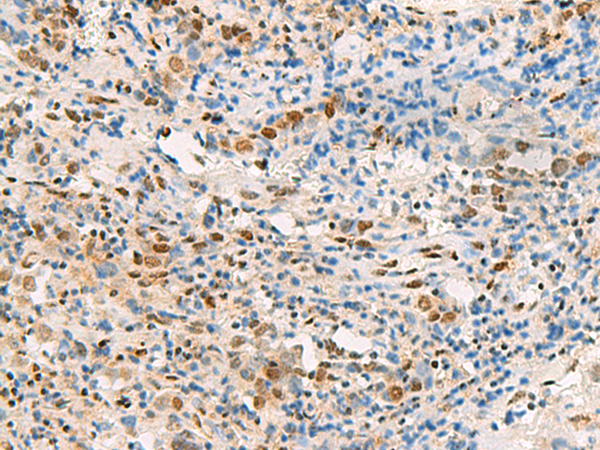

IHC positive control:

Human thyroid cancer and Human cervical cancer

IHC Recommend dilution:

25-100